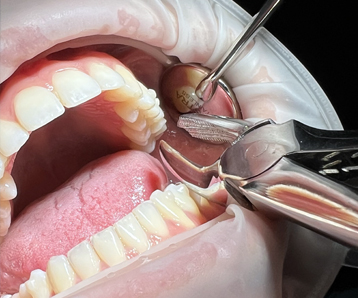

Cirugía oral

La cirugía oral comprende las técnicas quirúrgicas realizadas a nivel de la cavidad oral, como pueden ser: extracciones de muelas del juicio o de dientes incluidos, quistes, frenectomías, apicectomías y cirugía periimplantaria. Estas intervenciones se realizan generalmente con anestesia local, aunque en ocasiones se puede aplicar sedación con un anestesista.

Cada caso se valora de forma individual junto con el equipo interdisciplinario para obtener el mejor resultado en cada situación.